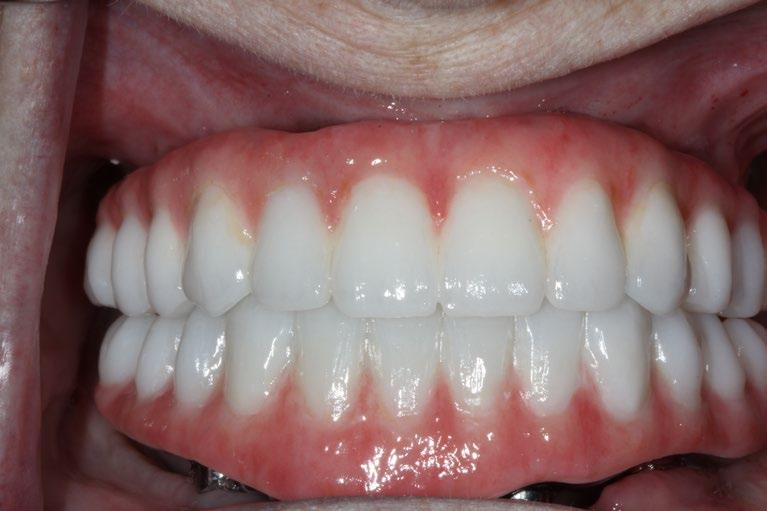

Creating a New Look with Dental Implants

One of the most significant advantages of dental implants is their ability to restore a natural-looking smile. They are customdesigned to match the natural color and shape of the patient’s existing teeth, blending seamlessly into the mouth. This can dramatically improve a person’s appearance, making them look younger and healthier. For many, this can lead to a renewed sense of self-esteem and vitality, particularly important as they age.

The Impact on Confidence

Beyond aesthetics, the functionality provided by dental implants plays a crucial role in boosting confidence among older adults. With age, many individuals face dental issues such as tooth loss, which can lead to difficulties in speaking and eating. Dental implants restore these capabilities to their fullest potential, allowing people to enjoy a variety of foods and speak clearly and confidently without the worry of slipping dentures.

Psychological and Social Implications

The psychological and social implications of a restored smile are profound. Studies show that a healthy, attractive smile can play a critical role in interpersonal interactions and social relationships, which are essential aspects of life, especially for the elderly. Being confident in one’s smile can lead to more social interactions, less social anxiety, and an overall better quality of life.